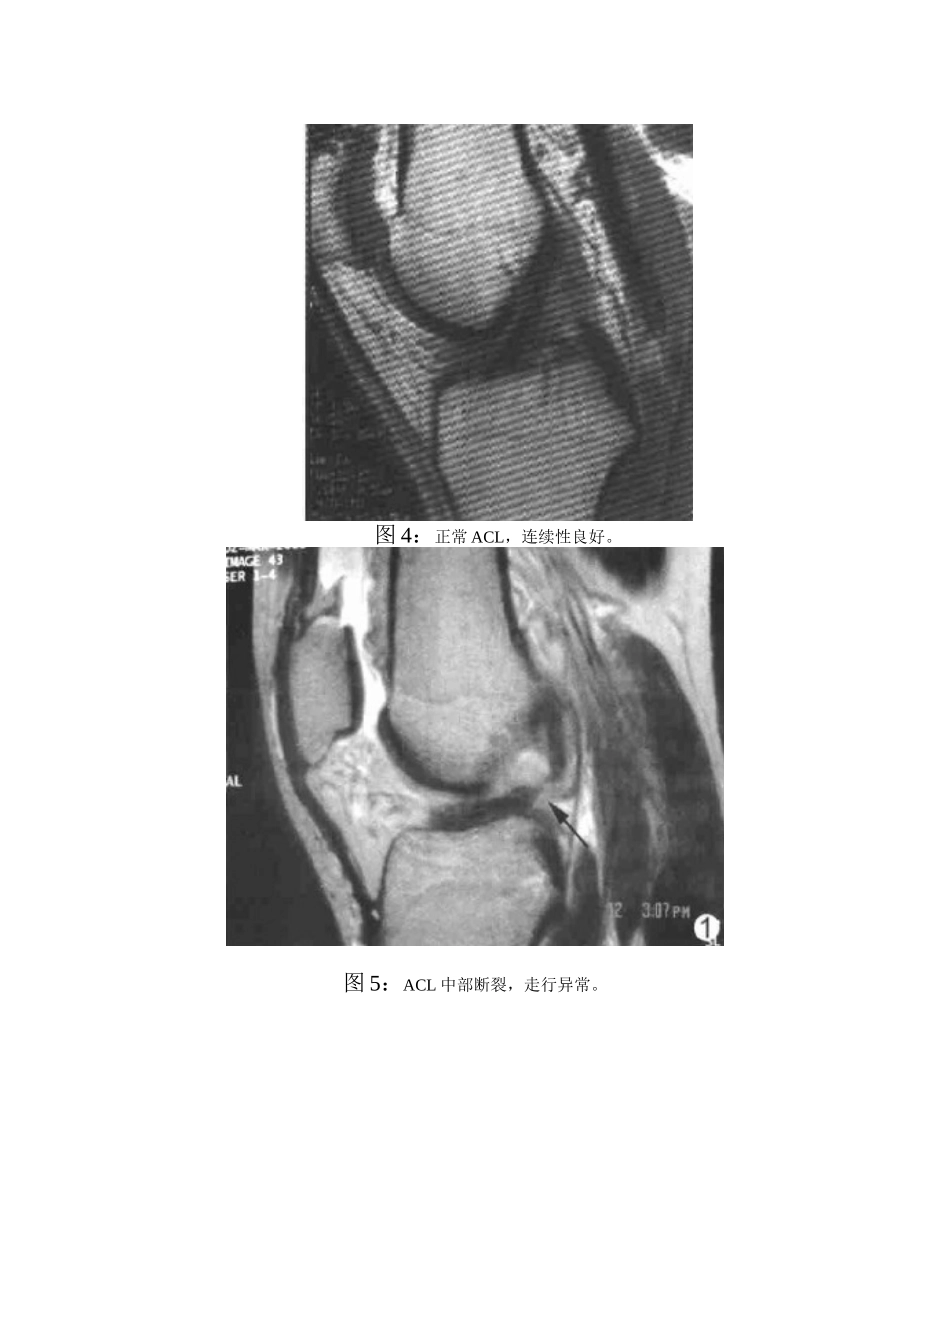

前交叉韧带损伤的治疗一、什么是前交叉韧带?在膝关节腔内有两条韧带,分别为前交叉韧带(ACL)和后交叉韧带(PCL),它们在维持膝关节的稳定性方面作用至关重要,其中前交叉韧带的作用有:(1)限制胫骨前移(2)限制过伸(3)限制内外旋活动(4)限制内外翻活动。其主要作用是限制胫骨前移。前交叉韧带(AnteriorcruciateLigament),它的股骨止点位于髁间窝外侧壁的后外上方。胫骨止点位于胫骨平台上胫骨脊的稍前内侧方。图1:膝关节解剖结构示意图二、前交叉韧带是如何损伤的?损伤后的表现?外伤时,有的患者觉膝关节内有撕裂声,随即出现膝关节软弱无力,关节疼痛,肿胀,关节内积血,不能继续运动或者行走困难。关节周围有皮下瘀斑者常表示合并关节囊损伤。在急性膝关节损伤中,前交叉韧带断裂可能是最易漏诊的损伤由于疼痛和肌肉痉挛,常规查体及X线检查难以作出准确诊断,因此,需要借助于特殊的辅助诊断手段,如MRI、关节镜检查。急性期过后,膝关节疼痛逐渐减轻,关节活动度逐渐恢复正常,可以行走、慢跑,但不能剧烈运动,尤其是不能快速跑,不能完成急停起跳等动作,经常伴有关节错动感。图2:膝关节前交叉韧带损伤示意图图3:膝关节前交叉韧带损伤时合并损伤统计图三、前交叉韧带损伤的诊断常规X线检查不能对前交叉韧带损伤作出准确诊断,MRI是目前诊断该病最敏感的无创检查手段。同时,MRI还可对膝关节的其他合并损伤进行诊断。前交叉韧带损伤可以有不同的MRI表现,但只要断裂或者部分断裂,都应该进行早期重建,以提高手术疗效,减少后遗症。图4:正常ACL,连续性良好。图5:ACL中部断裂,走行异常。图6:ACL断裂,水平走行。图7:ACL断裂,胫骨前移。图8:ACL断裂,合并股骨外髁骨挫伤。图9:ACL断裂,外侧半月板裸露。四、前交叉韧带损伤后如何治疗?前交叉韧带断裂时经常合并有邻近结构的损伤,如半月板损伤、内外侧副韧带损伤,因此,应该进行早期修复,重建断裂的前交叉韧带断裂,同时处理合并伤。我们采用关节镜微创技术对前交叉韧带损伤、后交叉韧带损伤和相关合并损伤的病人进行手术重建,手术创伤小,对膝关节干扰少,术后恢复快。图10:前交叉韧带重建时手术示意图图11:前交叉韧带重建时手术示意图五、前交叉韧带重建的手术效果如何?未及时处理有何后遗症?膝关节前交叉韧带损伤经过及时的手术治疗和正规的术后康复训练后,疗效良好,可以恢复大部分的运动功能及日常生活能力,同时也大大减少了前交叉韧带损伤后相关并发症的发生。若失去了早期修复的机会,常遗留下不同程度的膝关节不稳。不稳定的关节容易反复受伤,加速关节软骨、半月板等结构的损伤,导致肌肉萎缩或创伤性关节炎。晚期韧带重建方法很多,但远期效果不理想,不能完全恢复原韧带的功能,常遗留不同程度的关节功能障碍,许多患者被迫因此接受人工关节置换手术。图12:前交叉韧带损伤后导致创伤性关节炎示意图